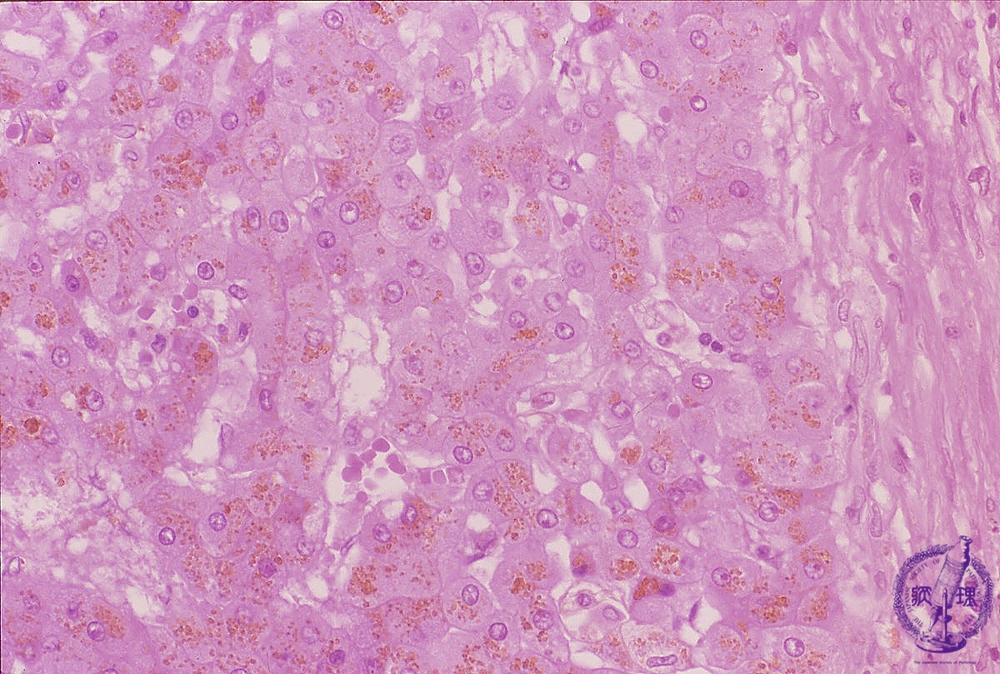

Microscopic image (HE stain, high power): Most of the hepatocytes within regenerative nodules contain coarse golden brown granular deposits (hemosiderin).